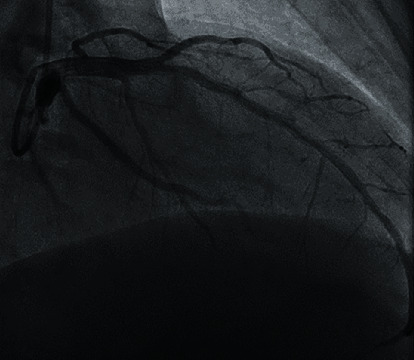

医源性主动脉夹层是经皮冠状动脉介入治疗(PCI)中一种罕见但可能致命的并发症。PCI术后的医源性主动脉夹层是罕见的,大多数病例报告夹层起源于冠状血管并扩散到升主动脉。本例剥离未累及冠状动脉,剥离从升主动脉延伸至降主动脉和髂血管。尽管经桡骨入路PCI的血管并发症比经股骨入路少,但仍可能发生明显的不良后果,需要及时干预。这个病例强调了高度不典型的医源性主动脉夹层在心导管置入后表现为急性肢体缺血。对于像我们这样的患者,由于整体预后不良,必须立即进行手术干预。

Iatrogenic aortic dissection is a rare but potentially fatal complication of percutaneous coronary intervention (PCI). Iatrogenic aortic dissection following PCI is rare with most cases reporting dissection originating within the coronary vessels with propagation into the ascending aorta. In this specific case, dissection was without coronary involvement, with dissection extending from the ascending aorta into the descending aorta and iliac vessels. Although PCI via radial approach is associated with fewer vascular complications than with femoral approach, significant adverse outcomes may still occur and require prompt intervention. This case highlights the highly atypical presentation of iatrogenic aortic dissection following cardiac catheterization presenting as acute limb ischemia. In such patients as with ours, immediate surgical intervention is necessary with overall poor prognosis.